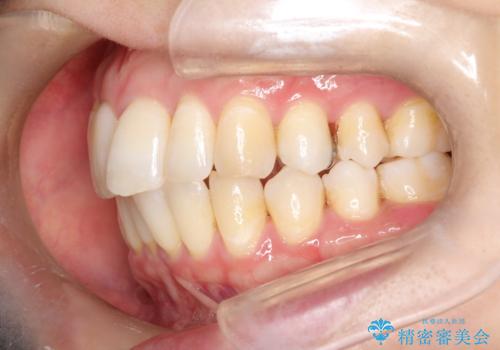

再矯正をインビザラインで目立たず手軽に

- 以前矯正をしていたが、わずかに後戻りをしてしまったのを主訴に来院されました。

装置はなるべくつけたくないとのことで、インビザラインにて治療することとなりました。

以前ワイヤー矯正をされていた方は、装置をつけての再矯正を希望されない方もいます。

その場合にインビザラインをお勧めさせていただいております。

後戻りがわずかな場合は、期間も短くて済む場合があります。